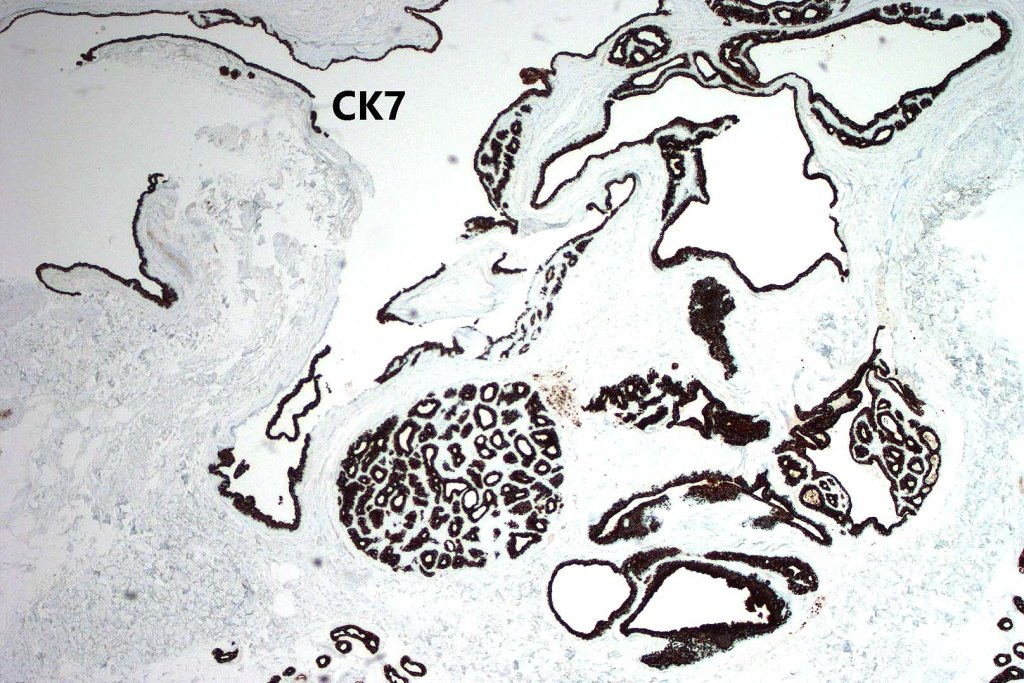

•CK7, CK18, GATA3, HMFG, GCDFP-15+ve

•Myoepithelial cells SMA, S100, p63 +ve